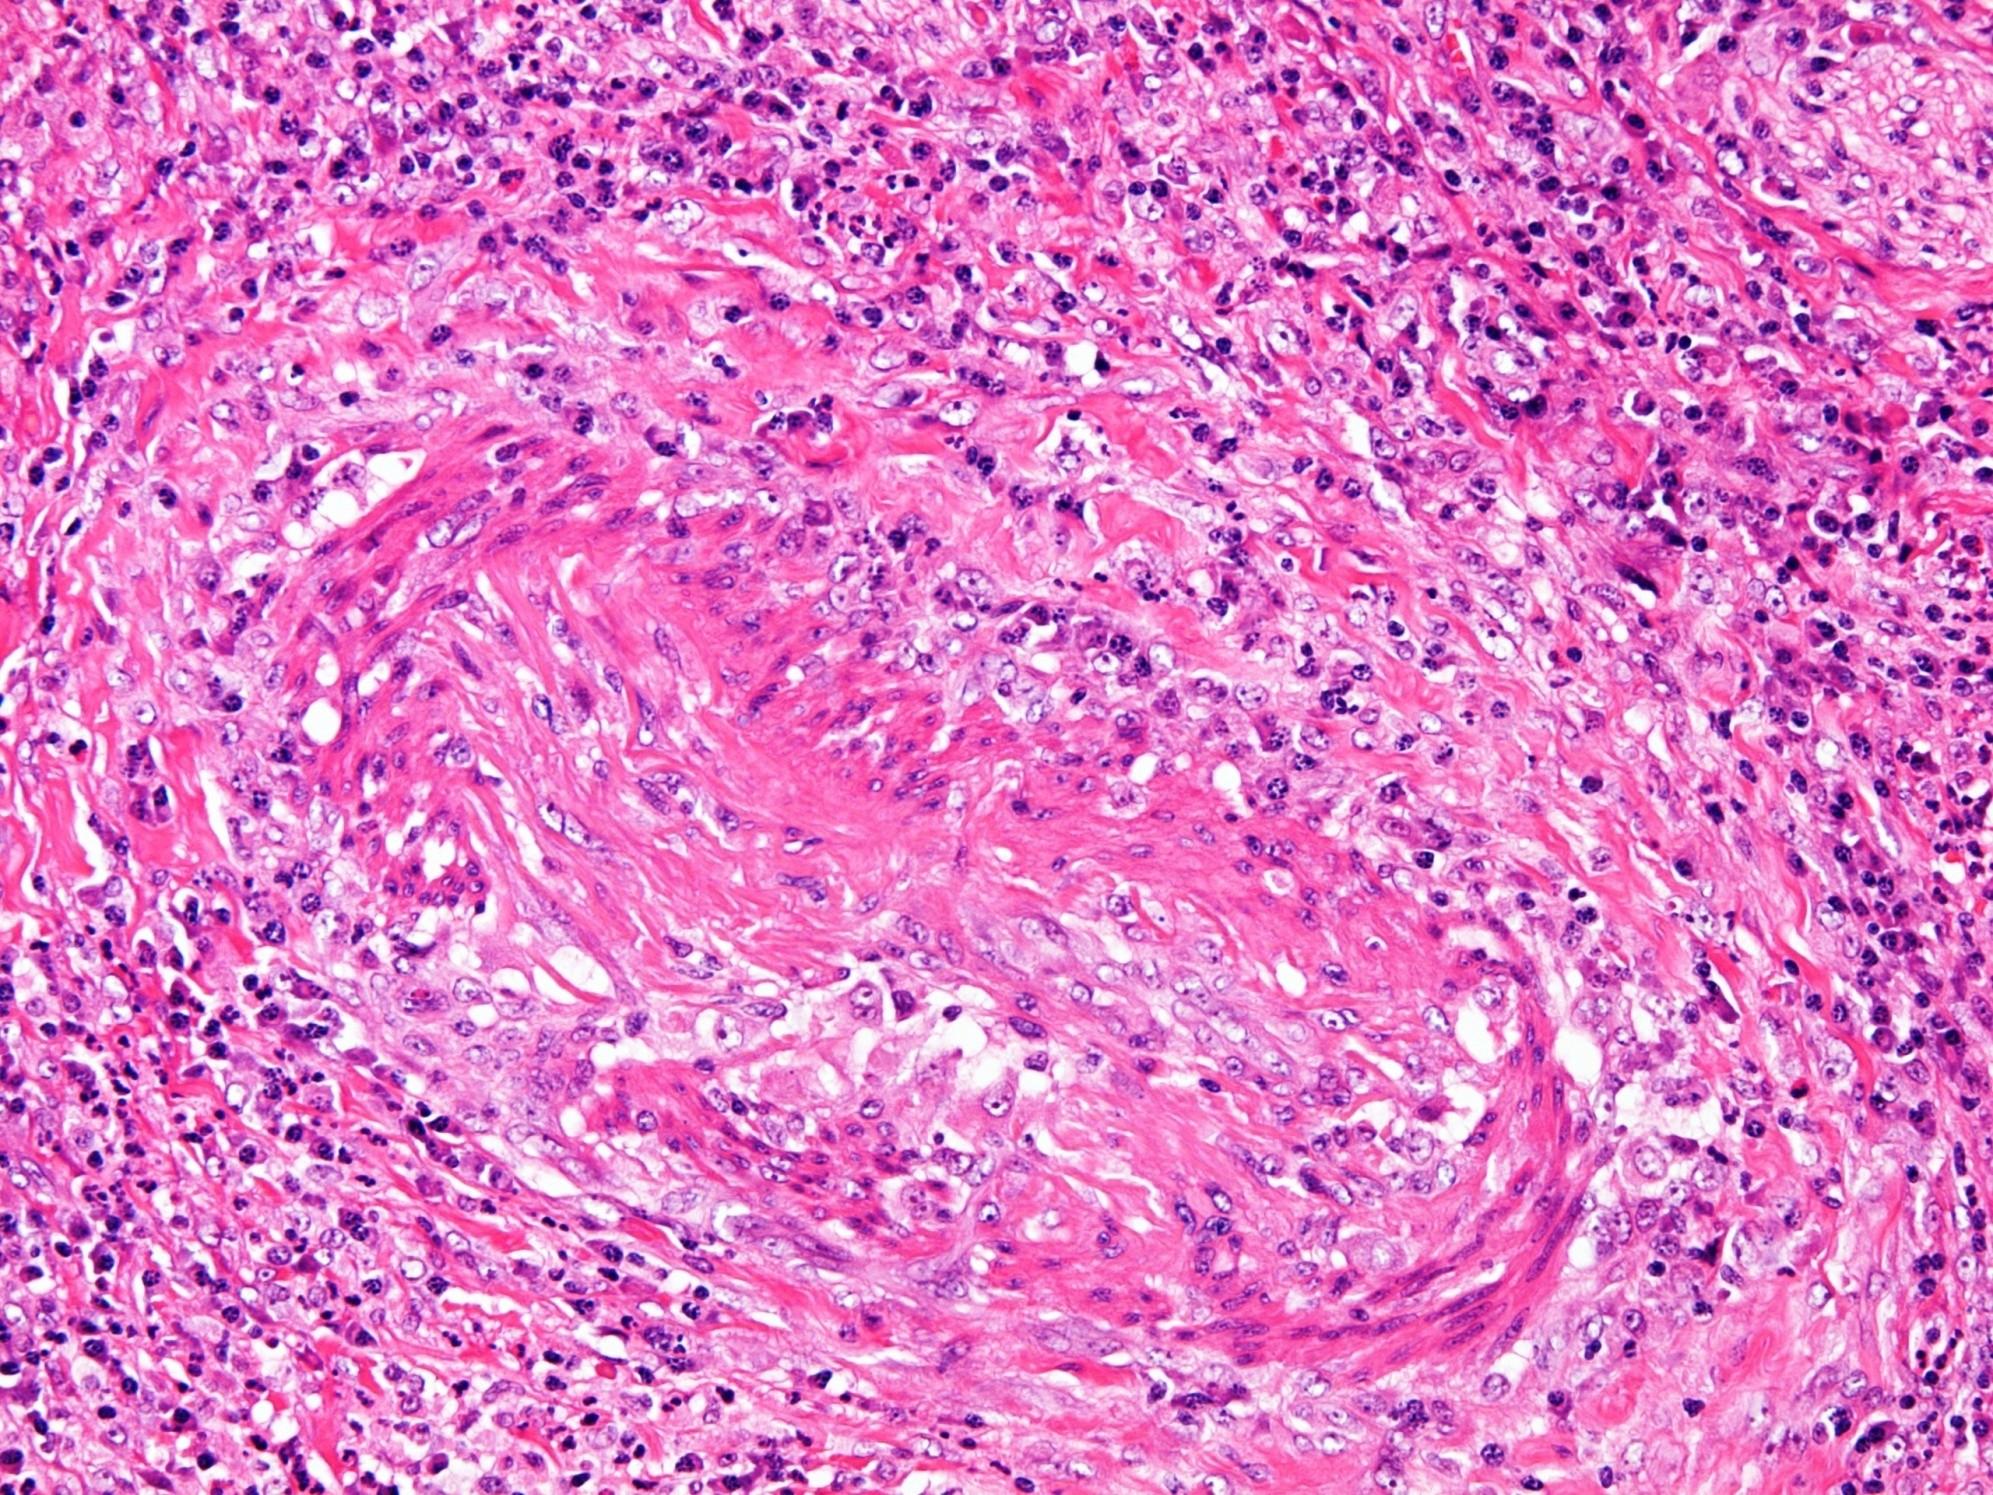

Wegener’s granulomatosis

 Systemic vasculitis and necrotising granulomatosis

 Upper and lower respiratory tracts and kidneys  cANCA positive

Triad

Necrosis

Vasculitis

Granulomatosis

 Mixed acute on chronic inflammation with neutrophilic microabscesses

 Eosinophils

 Giant cells unassociated with granulomas

 Geographic necrosis